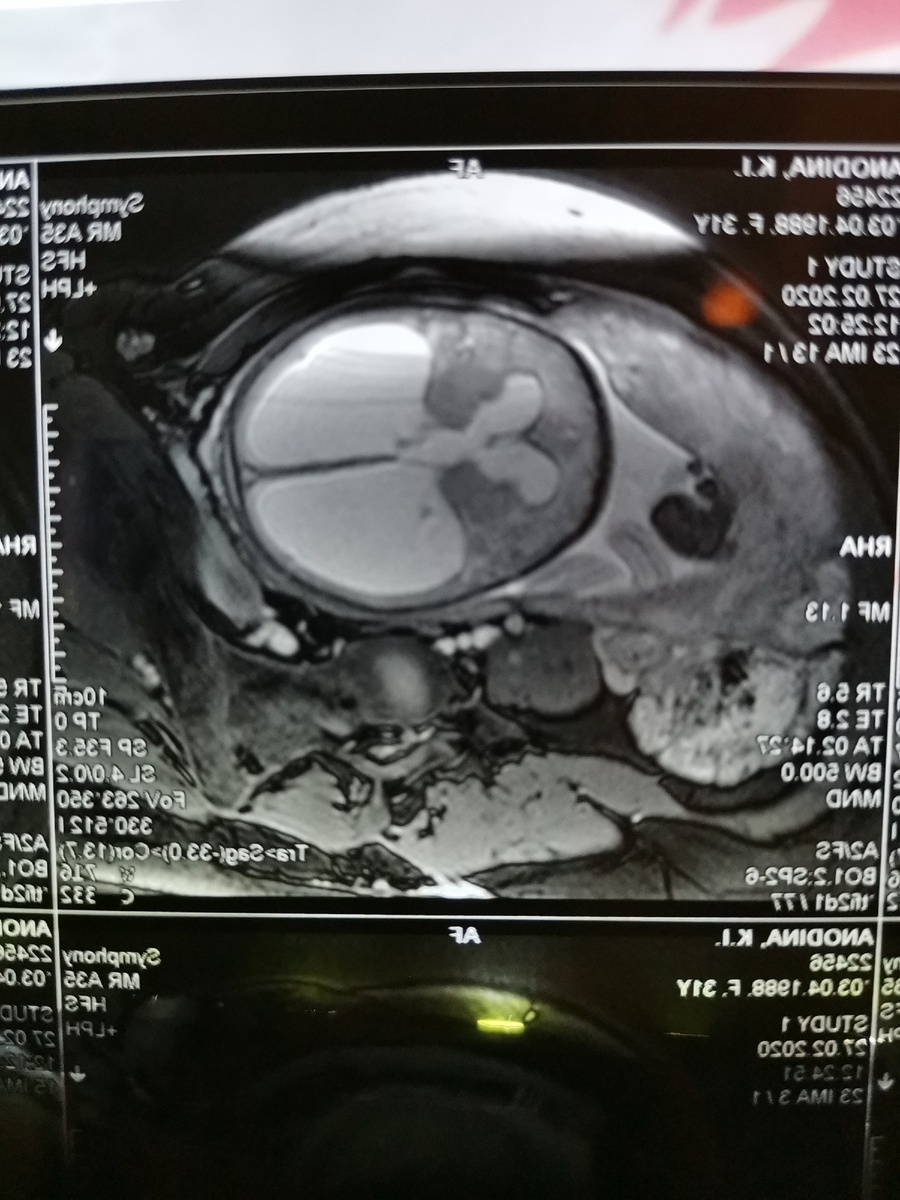

Начало как у многих любящих пар очень хорошее, свадьба, медовый месяц, запланированая беременность, и все шло хорошо, до 13 февраля 2020 года, в этот день мне сделали 3й скрининг и домой я вернулась без сил, причиной тому стала Врожденная Гидроцефалия головного мозга у ребенка, и это была 33я неделя беременности..... И самое страшное в этом, было то, что даже врачи не знали что делать...т.к.врожденно,по их словам развивается редко, для точности боковые желудочки были под 45мм,3й желудочек был около 15мм,объем головы уже был 38см,как на момент родов должна быть.. для полного понимания в норме боковые должны быть максимум 10мм и 3й около 4мм,т.е.в нашем случае у долгожданной дочери они были расширены ликвором в 4 раза((((

Мозг сохранился только в лобной части...

Там где белое в голове, это не мозг, это все ликвор.....

С УЗИ в консультации я была отправлена в Медецинский Генетический Центр на выборгской, возможно кто то скажет, что там хорошо, но там я услышала "гениальную фразу", 1ю от Узиста, который смотря на направление, спросил у меня, что за диагноз, 2ю от генетика "Попробуйте в следующий раз", отправили в Роддом на Консилиум, перед ним естественно на мрт, без него никак, фото выше)